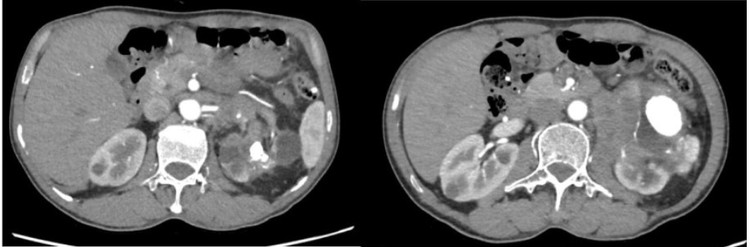

| Hình ảnh phim chụp cắt lớp ổ bụng có sỏi thận và khối u thận của người bệnh - Ảnh BVCC |

Bệnh nhân Đỗ V P (64 tuổi, ở TP Hạ Long, Quảng Ninh) khám tại Bệnh viện Bãi Cháy do đau tức thắt lưng kéo dài, tiểu buốt, tiểu đục. Kết quả siêu âm, chụp CTscanner ổ bụng phát hiện thận trái có nhiều sỏi kích thước lớn 50x69mm ở đài bể thận, giãn bể thận, vùng rốn thận có khối u kích thước 40x44mm xâm lấn tĩnh mạch thận trái, dính vào động mạch chủ bụng và tổ chức xung quanh, nhiều hạch vùng rốn thận kích thước lớn nhất 12x16mm.